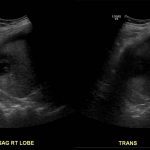

- Heterogeneous hypoechoic lesion in the periphery of the right hepatic lobe measuring up to 5.5 cm without internal vascularity

- Hepatomegaly with coarsened hepatic parenchymal echotexture

- Small volume, heterogeneous appearing perihepatic fluid

Heterogeneous hypoechoic lesion in the periphery of the right hepatic lobe measuring up to 5.5 cm without internal vascularity, concerning for an abscess. Adjacent small volume complex ascites raises concern for intraperitoneal rupture.

Hepatomegaly with coarsened hepatic parenchymal echotexture, concerning for cirrhosis.

- Depending on the internal contents, abscesses may appear predominantly hyper- or hypoechoic and may mimic solid liver masses